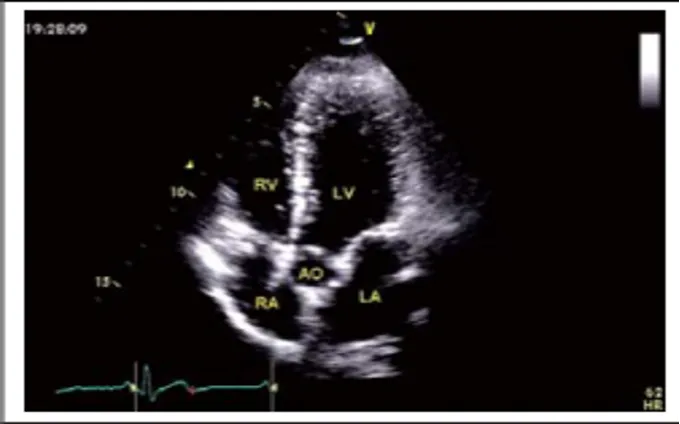

剑突下四腔心切面

探头位置:探头位于剑突下声速指向左肩。

观察内容:4个房室腔;二尖瓣、三尖瓣、房间隔、室间隔。

剑突下大动脉短轴切面

探头位置:剑下四腔心切面顺钟向转动探头90°。

观察内容:同胸骨旁大动脉短轴切面。